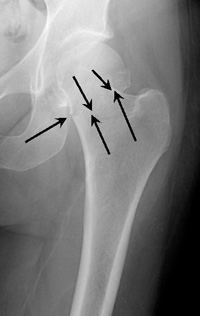

Intracapsular Fracture. This fracture occurs at the level of the "neck" of the bone and may have loss of blood supply to the bone.

Intertrochanteric Fracture. This occurs further down the bone and tends to have better blood supply to the fracture pieces.

These fractures occur at the level of the neck and the head of the femur, and are generally within the capsule. The capsule is the soft-tissue envelope that contains the lubricating and nourishing fluid of the hip joint itself.

This fracture occurs between the neck of the femur and a lower bony prominence called the lesser trochanter. The lesser trochanter is an attachment point for one of the major muscles of the hip. Intertrochanteric fractures generally cross in the area between the lesser trochanter and the greater trochanter. The greater trochanter is the bump you can feel under the skin on the outside of the hip. It acts as another muscle attachment point.